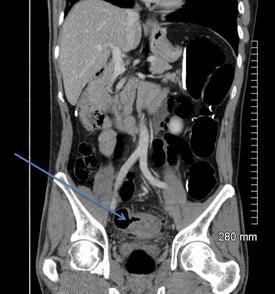

A 52-year-old man with a benign stricture, categorized as C4E1D4. The arrows highlight the smooth gradual transmural thickening within a diverticular laden sigmoid colon. Benign stricture was confirmed with surgical resection.

In terms of pathology within the D3 and D4 categories, 60 cases showed sigmoid diverticular disease on imaging, 10 showed sigmoid strictures, diverticular abscesses were found in five cases, and two cases included Crohn's or ulcerative colitis, they reported. Within the D3/D4 category, 24% underwent further intervention, either surgical (eight cases) or endoscopic (12 cases).